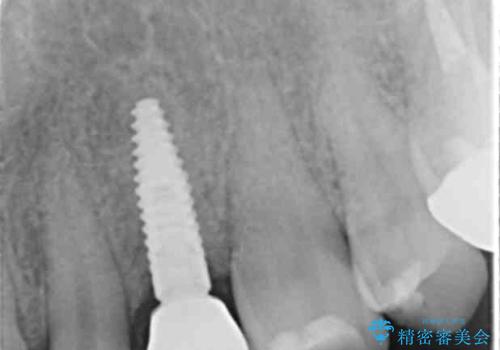

[奥歯がなくて噛めない] インプラントによる咬合回復

- 奥歯を喪失し、食事がうまくできないことの改善希望され来院されました。

奥歯がないので義歯(入れ歯)、もしくはインプラント治療を提案し、しっかり噛みたいとの希望からインプラントを用いての咬合回復を計画しました。

インプラントは奥歯がない場合に噛み合わせを回復できる、義歯(入れ歯)に変わる有用な手段です。

しかし、長期的な予後を満たす要件としてインプラントが歯周病菌に感染しないこと(清掃性)、安定した咬合,安定したインプラント周囲の組織(骨・歯肉)を獲得することが重要です。

今回インプラント周囲には毎時に骨の増成、2次手術時に角化歯肉の移植を行うことで清掃性を高め安定した環境を得ることができています。